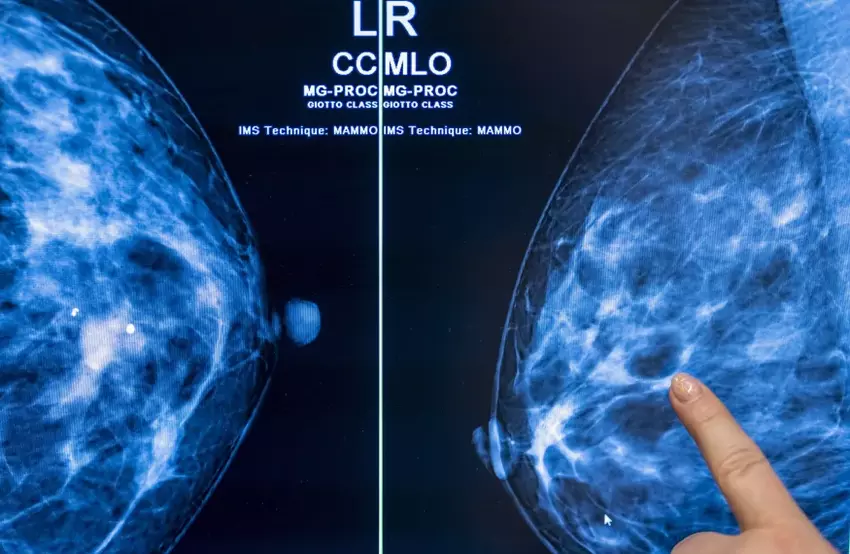

Het gebruik van kunstmatige intelligentie bij kankerscreening op basis van mammografie zou de werklast van de radioloog veilig met bijna de helft kunnen verminderen zonder het risico te lopen dat het aantal fout-positieven toeneemt.

In het onderzoek, dat werd uitgevoerd door een team wetenschappers van de Universiteit van Lund in Zweden, werden 80.033 vrouwen gedurende iets meer dan een jaar gevolgd. Van de 39.996 patiënten die willekeurig werden toegewezen aan borstkankerscreenings met AI, bleek 28% een kankergezwel te hebben.

Van de overige 40.024 patiënten die conventionele screening ondergingen, werd slechts in 25% van de gevallen kanker ontdekt.

Het percentage fout-positieve uitslagen voor zowel AI als conventionele screening was 1,5 procent. Van cruciaal belang is dat radiologen die met AI werkten 36.886 screenings minder hoefden te beoordelen dan hun collega's. Dit verminderde hun werklast met 44%. Dit verminderde hun werklast met 44%.

"Door AI ondersteunde mammografiescreening resulteerde in een vergelijkbaar kankerdetectiepercentage vergeleken met standaard dubbel lezen, met een aanzienlijk lagere werklast bij het screenen, wat aangeeft dat het gebruik van AI bij mammografiescreening veilig is", concludeerde het onderzoek.